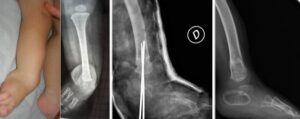

In fibular hemimelia, it is preferable to correct the foot and ankle deformity early (18-24 months of age)

and maintain it as the child grows, rather than having them walk with their foot in the deformed position. Various procedures have been described for this purpose, depending on the type of deformity present. The various alterations present (residual fibular joint, ankle valgus, subtalar fusion, peroneal and Achilles tendon contracture, etc.) are corrected to ensure good foot support.

The combination of all these procedures, in the most severe cases of fibular hemimelia , is called the SUPER-Ankle procedure (Paley D, J Child Orthop 2016: Surgical reconstruction for fibular hemimelia)